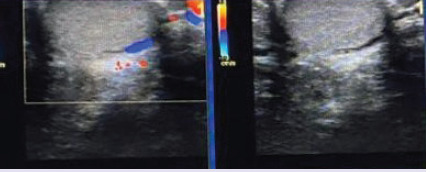

Objective: Only few cases of intratesticular varicocele (ITV) have been reported in the literature, mostly as single cases or a case series. In this study, we aimed to describe the topographic distribution of ITVs in the testicular parenchyma and the correlation between ITV accompanying extratesticular varicocele (ETV) and age.

Methods: Approximately 10,537 patients with scrotal pain and swelling who visited our hospital between August 2014 and May 2020 and underwent scrotal colour Doppler ultrasonography were included in this study. Of these patients, 2285 had ETV, and the remaining patients (n=8252) had other testicular pathologies such as acute-chronic torsion, testicular mass, orchitis, significant testicular atrophy, or isolated extratesticular varicocele, and were thus excluded from the study. Among the 2285 patients, only 20 had ITV.

Results: Of the 20 patients with ITV, 2 had isolated ITV, and the remaining had ITV accompanying ETV, of whom only one had a right ETV. One patient had left testicular atrophy accompanying an isolated ITV. Among the ITV cases, subcapsular ITV was the most common (n=13), followed by central ITV (n=4) and subcapsular and hilar ITV (n=3). The patients' ages ranged from 18 to 30 years.